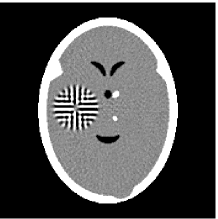

Furthermore, we used the classic ART iteration as the iteration operator in our numerical experiments. In order to compare the proposed superiorization algorithm with the classic superiorization algorithm, we applied the classic superiorization and -PP superiorization algorithm to two phantoms (see figure 1). The first one is the Shepp-Logan phantom[30], and the second one is the head phantom with a ghost which is invisible at 22 specified projection directions [10, 31]. In addition, we compare the performances of the two algorithms for the noiseless and noised data with different projections. In all experiments, the noised projection data was corrupted by additive Gaussian white noise with variance . We record the iterations, running time of program and mean square error (MSE) of different algorithms, where MSE is computed by

3.2 Ghost phantom

Noiseless projection data: Since the ghost in this phantom is invisible at 22 directions [10, 11], the reconstruction images usually suffer from artifacts. in our simulations, the projection data were collected in 112 and 82 directions: 90 and 60 with equal angle increments from to and 22 specified views in which the ghost is invisible [10]. Iteration procedures were terminated when for the noiseless projections.

Noised projection data: For the noised projection data, the iteration processes were terminated when for 82 and 112 projections. The reconstruction images were given in Fig. 7. Table 4 showed the MSEs, iterations and running time of program of the results of images in Fig. 7.

By comparing the images in Fig. 6, 7 and numbers in Table 3, 4, we can obtain the same conclusions that the proposed perturbation can not only improve qualities of reconstructed images, but also can accelerate the convergent speed. However, we can observe that the reconstruction images suffer from artifacts regardless of the classic and the proposed algorithm when the projections is inadequate.